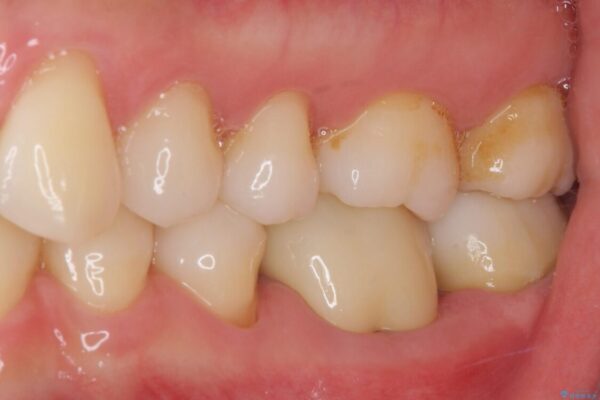

以前他院にて処置をした歯の歯肉からの出血するとのことで来院された患者様です。

以前むし歯治療をした後から定期的に痛むことがあるとのことで、レントゲン写真より神経組織が失活していることが予想されました。

銀歯を外すと神経組織の一部が取り除かれており、歯根に付け根に穴が空けられている状態でした。

出血の原因は以前の治療で空けられた穴であると考え、封鎖をするとともに根管治療を行い、その後オールセラミッククラウンにて補綴治療を行うこととしました。

治療前

• むし歯で歯茎から血が出てくる オールセラミッククラウンでの補綴治療 治療前画像